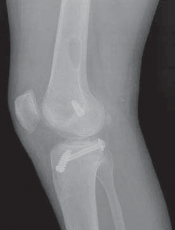

8. Radiographs of the knee should be performed following an acute injury to assess for a fracture. An avulsion of the tibial insertion of the PCL may be identified on a lateral radiograph (

FIG 1A

).

FIG 1 • A. Avulsion fracture of the tibial insertion of the posterior cruciate ligament (PCL). B. Posterior subluxation of the

tibia in a case of chonic PCL deficiency.

1. In the chronic setting, radiographs may identify posterior tibial subluxation (

FIG 1B

) or medial and patellofemoral compartmental arthrosis.